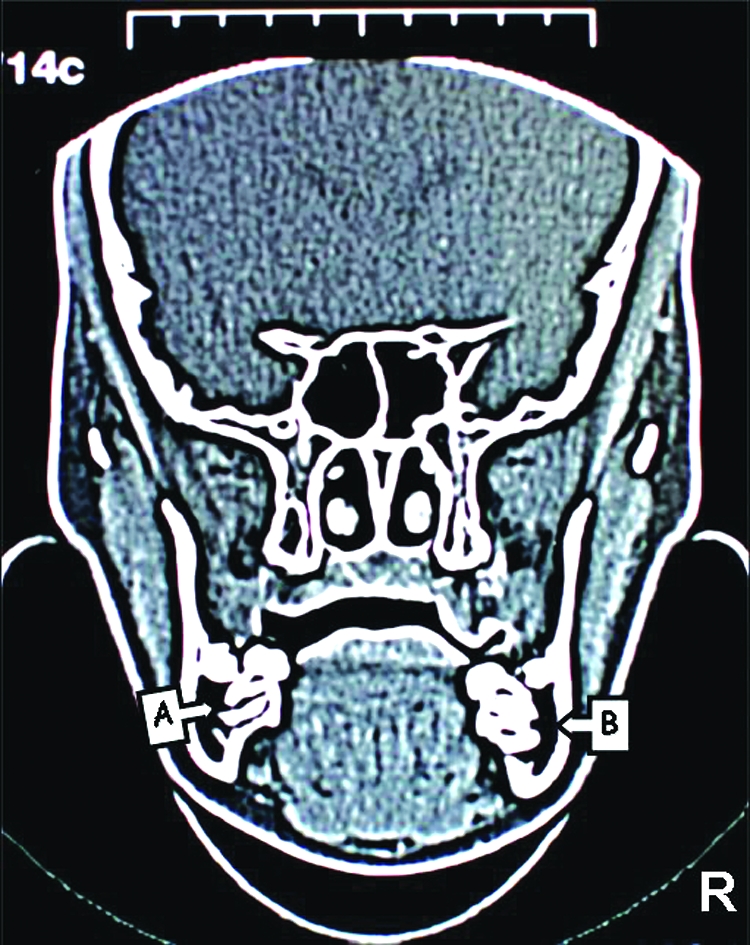

Figure 4.

CT images of the patient. The position of right inferior dental canal can be seen clearly as a dark area but left inferior dental canal cannot be seen due to the impacted second premolar. (A; Right Mandibular Canal, B; Left Mandibular Canal, C; Tipped Right First Molar, D; Impacted Right Second

In order to assess the position of the inferior alveolar canal and the relationship between the canal and second premolar a coronal, CT was taken (Philips Tomoscan, Netherlands). CT scanning of the mandible consisted of 26 slices with a thickness of 3mm and 1mm slice gap. Relationship of inferior alveolar canal and impacted premolar can be observed in Figure 4. Furthermore the amount of bone volume of the involved section and symmetrical section (to compare the bone volume) calculated from the slices on post processing screen of the system. The bone volume was 8.46cm3 on the right side compared to 12.75cm3 on the opposing side which demonstrated that the structural weakness could arise, if molar, premolar and primary second molar were extracted. This could lead to long term problems such as potential pathological fracture of the mandible.

In addition to the plain radiographies a CT was taken, due to the difficulties of locating the inferior alveolar neurovascular bundle in our case, which enabled us to determine the involved area more precisely for ensuring the vital structures are protected. The bone volume was calculated 8.46 cm3 on the right side and 12.75 cm3 on the opposing side from post processing screen of the system. This may imply extensive bone removal is required for extraction of the affected teeth which may predispose mandible to pathological fracture. Besides the possibility of eruption of second premolar was not considered in our case Premolar) as the tooth had curved root shape. Moreover, CT images revealed that mandibular nerve passes the impacted teeth in a very close proximity. Damage to the inferior alveolar nerve during the process of removal of the impacted teeth is highly likely. Previous reports documented that multiple impacted teeth were only observed with no surgical exposure or orthodontic traction due to the risk of extensive bone loss after surgical intervention.1,23